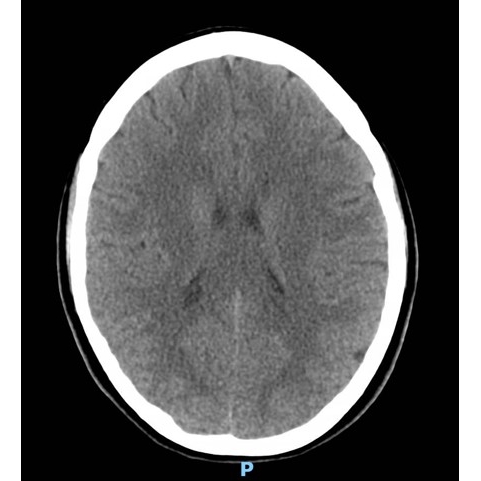

CT Head Case Photo #1 , CT Head/Neck Case Photo #2 , Brain MRI [Photo3] and CT Chest Case Photo #4 were all normal.